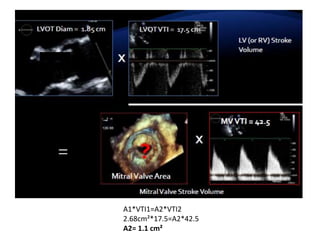

Ecuación de continuidad del área valvular

• Si es necesaria una evaluación adicional de la gravedad de la estenosis mitral,

puede calcularse un área valvular por ecuación de continuidad.

• Para obtener el área de la válvula mitral, se divide el volumen sistólico (VS)

transmitral por la integral de velocidad-tiempo del flujo de estenosis mitral

(IVTEM):

AVM = VS/IVTEM

Puntos clave:

• El volumen sistólico transmitral se determina en el tracto de salida del VI

(TSVI) o a través de la válvula pulmonar.

• Este cálculo solo es exacto en ausencia de insuficiencia mitral.

A1*VTI1=A2*VTI2

2.68cm²*17.5=A2*42.5

A2= 1.1 cm²

Paso 2: Evaluarla gravedad de la EM cont… Ecuación de continuidad del área valvular • Si es necesaria una evaluación adicional de la gravedad de la estenosis mitral, puede calcularse un área valvular por ecuación de continuidad. • Para obtener el área de la válvula mitral, se divide el volumen sistólico (VS) transmitral por la integral de velocidad-tiempo del flujo de estenosis mitral (IVTEM): AVM = VS/IVTEM Puntos clave: • El volumen sistólico transmitral se determina en el tracto de salida del VI (TSVI) o a través de la válvula pulmonar. • Este cálculo solo es exacto en ausencia de insuficiencia mitral.